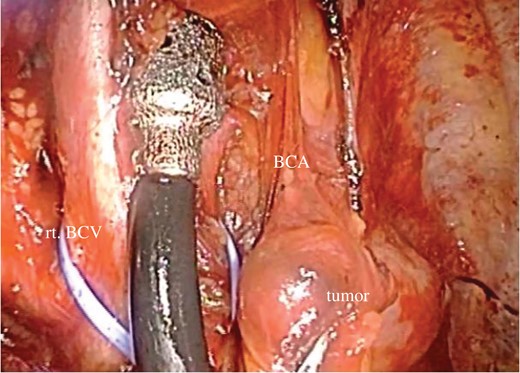

Here, we report a case of primary hyperparathyroidism due to a mediastinal parathyroid adenoma that was managed successfully by thoracoscopic resection. In this case, detailed preoperative information and magnified visual fields through thoracoscopy led to correct tumor identification during surgery, despite dense adhesions due to pleurisy. Thus, VATS resection should be the recommended treatment for functioning mediastinal parathyroid adenoma.

Chest CT (A) and MRI (B) revealed a mediastinal nodule adjoining the BCA.

In general, surgical approach for mediastinal tumor depends on its location and extension, including cervical approach, thoracotomy, and median sternotomy. Thoracoscopy provides magnified visual fields with small skin incision, which is especially useful for localization of small nodules [6, 7].